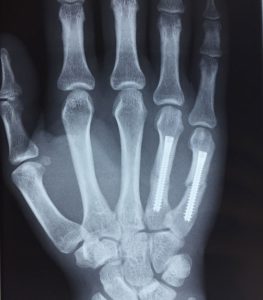

Fracturas de metacarpianos: (Figura 3) Muy habituales, especialmente las fracturas del boxeador, que afectan al cuello del quinto metacarpiano (Figura 4). Aparecen tras golpes con el puño mal cerrado y pueden necesitar inmovilización con férula, aunque algunas se tratan quirúrgicamente si hay desplazamiento. También se lesionan los otros metacarpianos por impactos repetidos o directos. Las fracturas desplazadas pueden requerir osteosíntesis.

Figura 3 - Fractura de metacarpianos sintetizadas con tornillos.